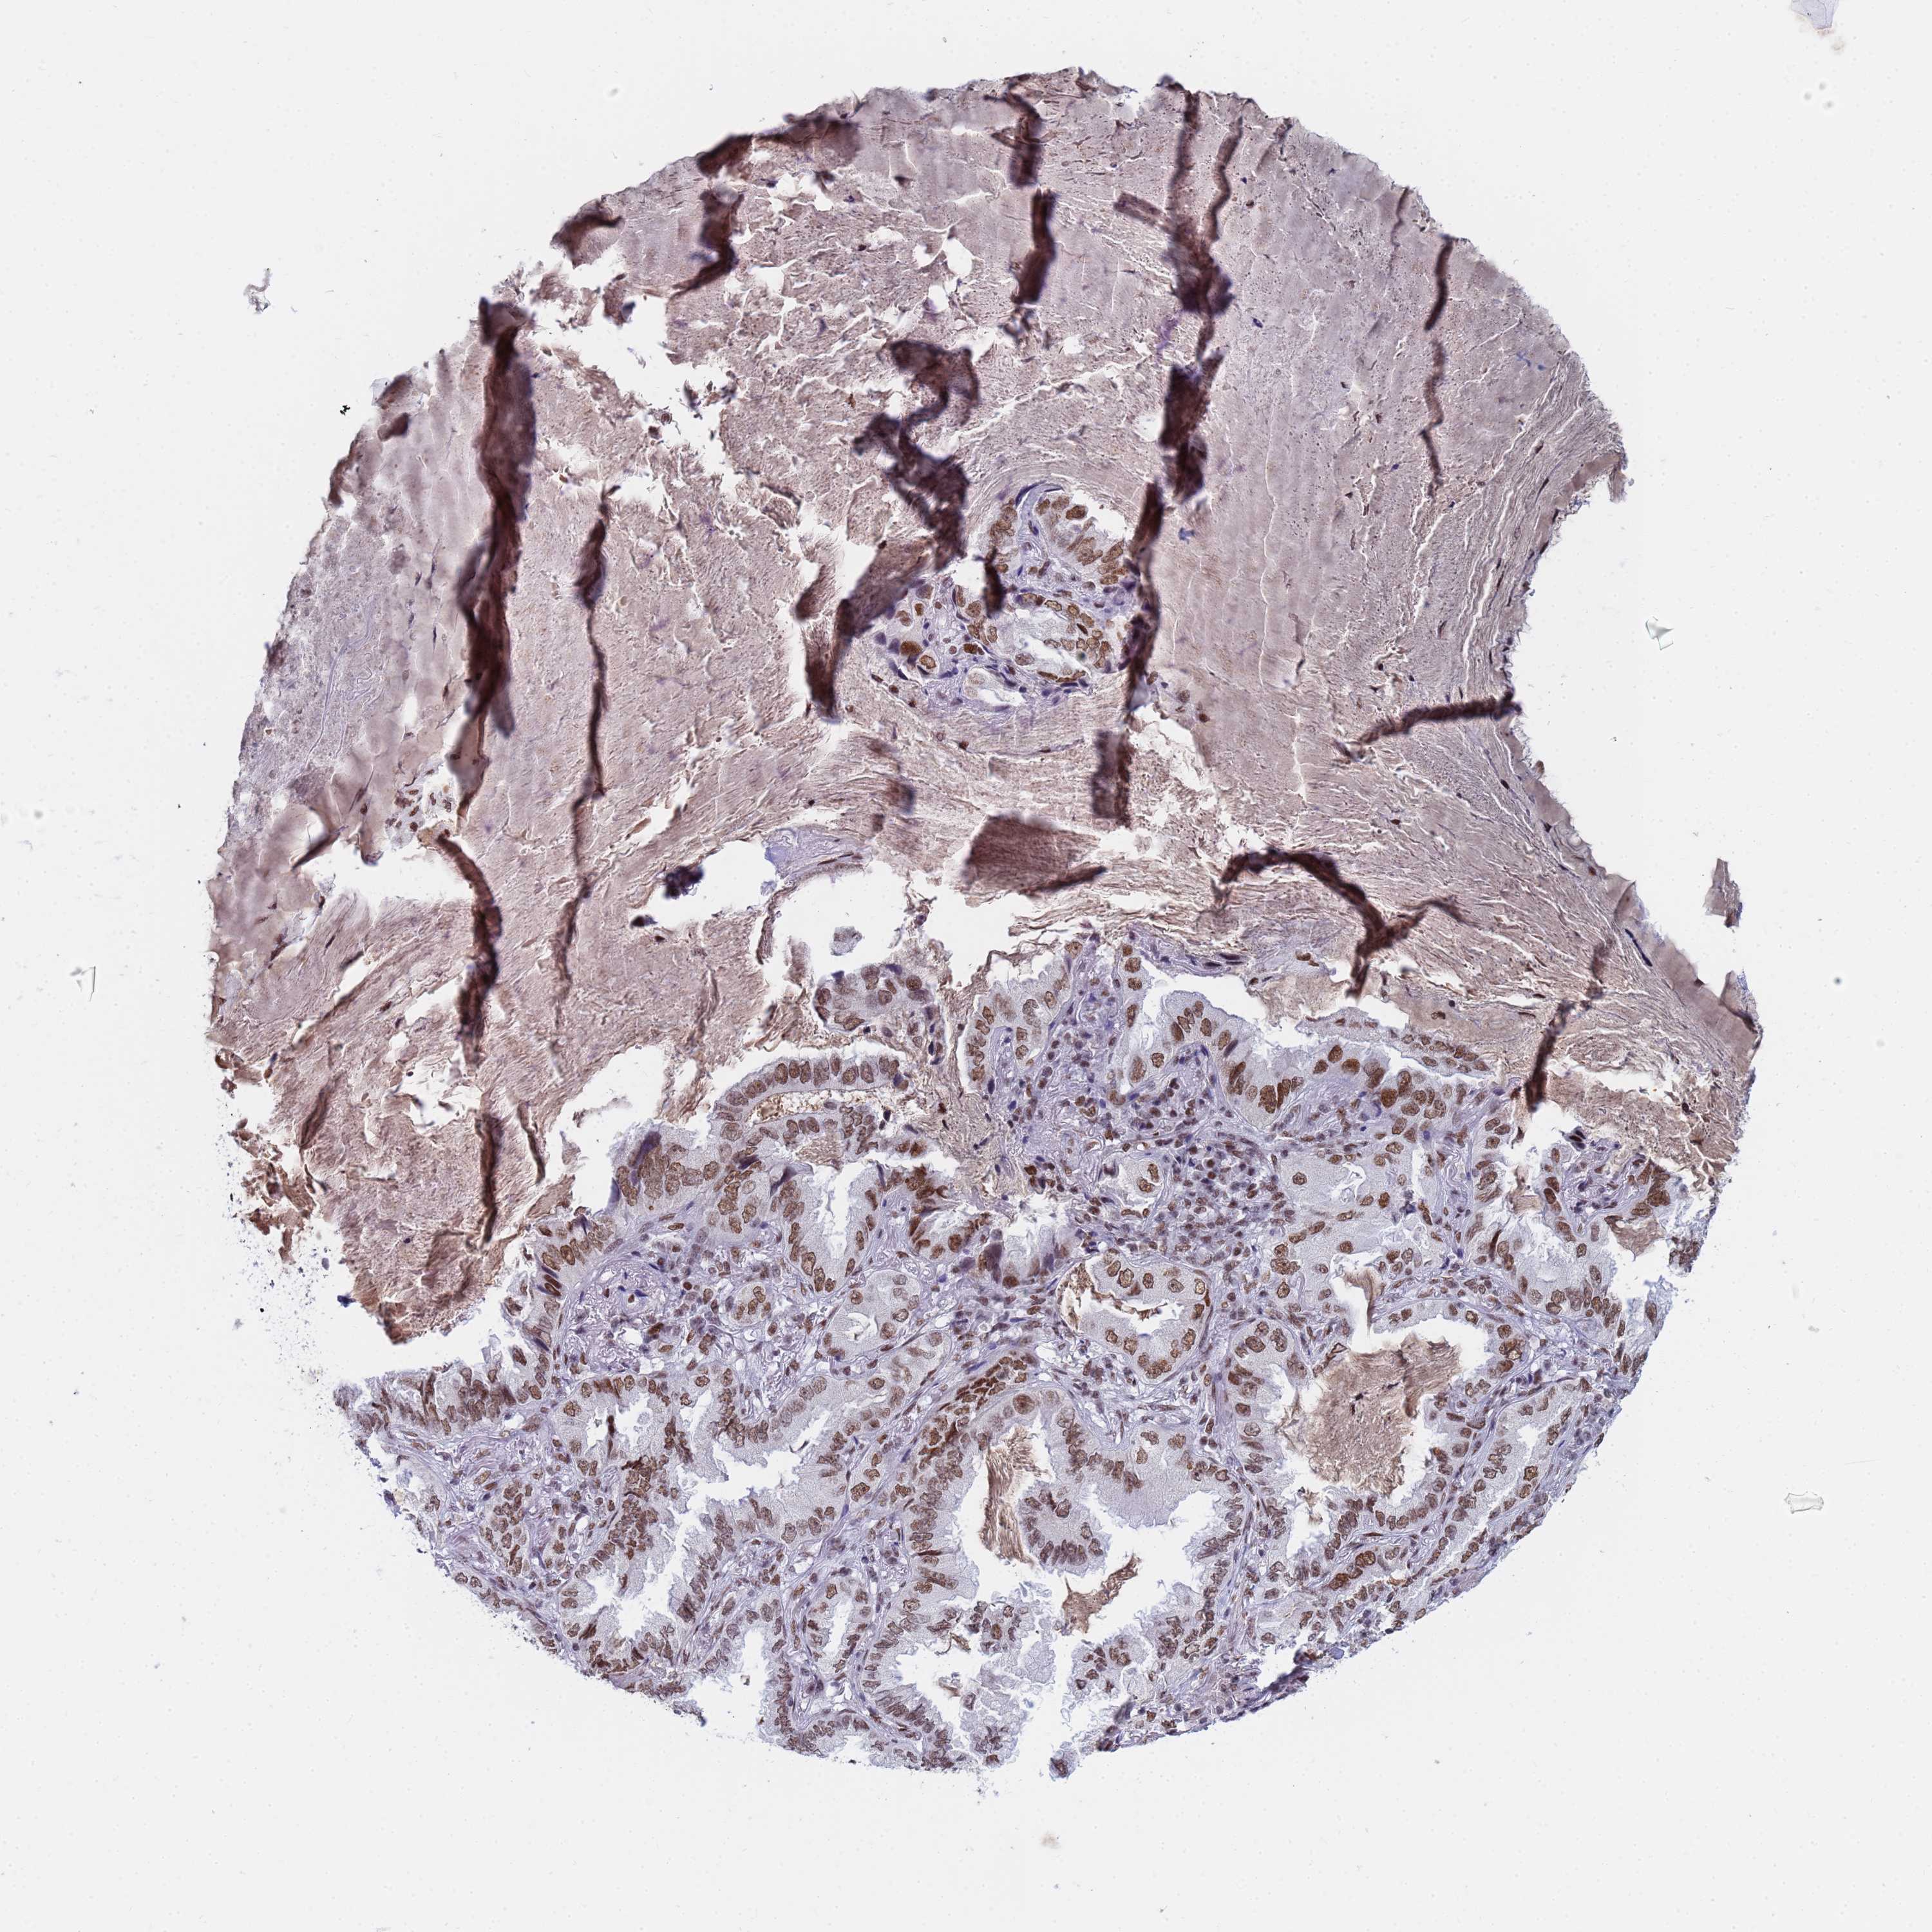

CANCER LUNG CANCER Show tissue menu